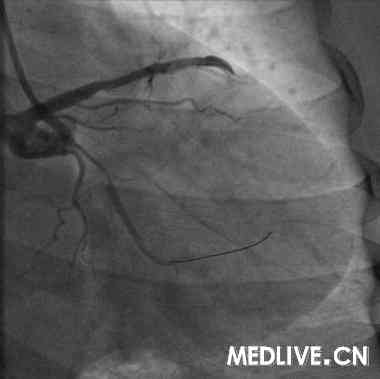

术前血管造影(附图):

冠造结果(图2-4):回旋支中段100%闭塞;右冠中段100%,并见大量血栓影;前降支中段不规则狭窄50%。结合临床,考虑右冠为急性心肌梗死相关冠脉,应首先对其进行急诊介入治疗。